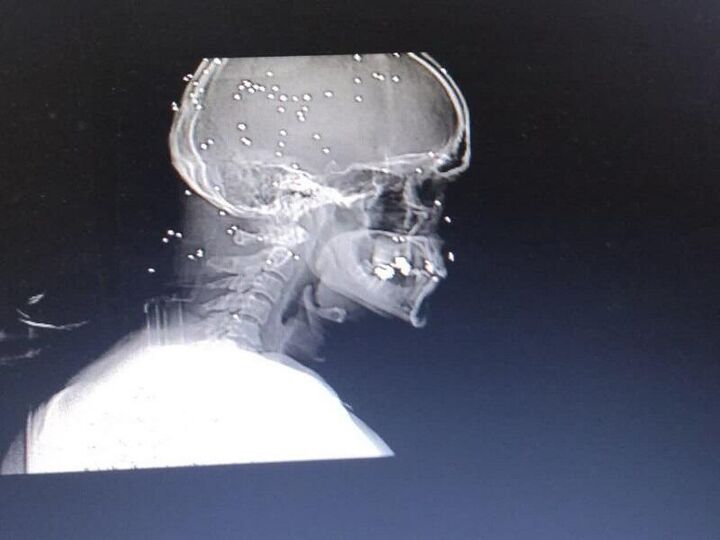

۴۳ ساچمه در مغز؛ تاوان حفاظت از مسجد

در پی اغتشاشات هفته گذشته در مشهد عده‌ای تروریست مسلح یکی از خادمان مسجدی در محله قاسم‌آباد را مورد حمله قرار دادند و ۴۳ ساچمه به سمت مغز این خادم شلیک کردند.

این خادم ایثارگر و شجاع توسط تروریست‌های خرابکار از ناحیه سر مورد اصابت گلوله قرار می‌گیرد و ۴۳ گلوله ساچمه‌ای در مغز و سر او جا خوش می‌کنند.

او غیرتمند که نخواست نامی از او برده شود؛ اکنون در بیمارستان تحت مداوا است ولی تمام ساچمه‌ها در وضعیتی خطرناک در مغز و اطراف نخاع او پراکنده شده‌اند.